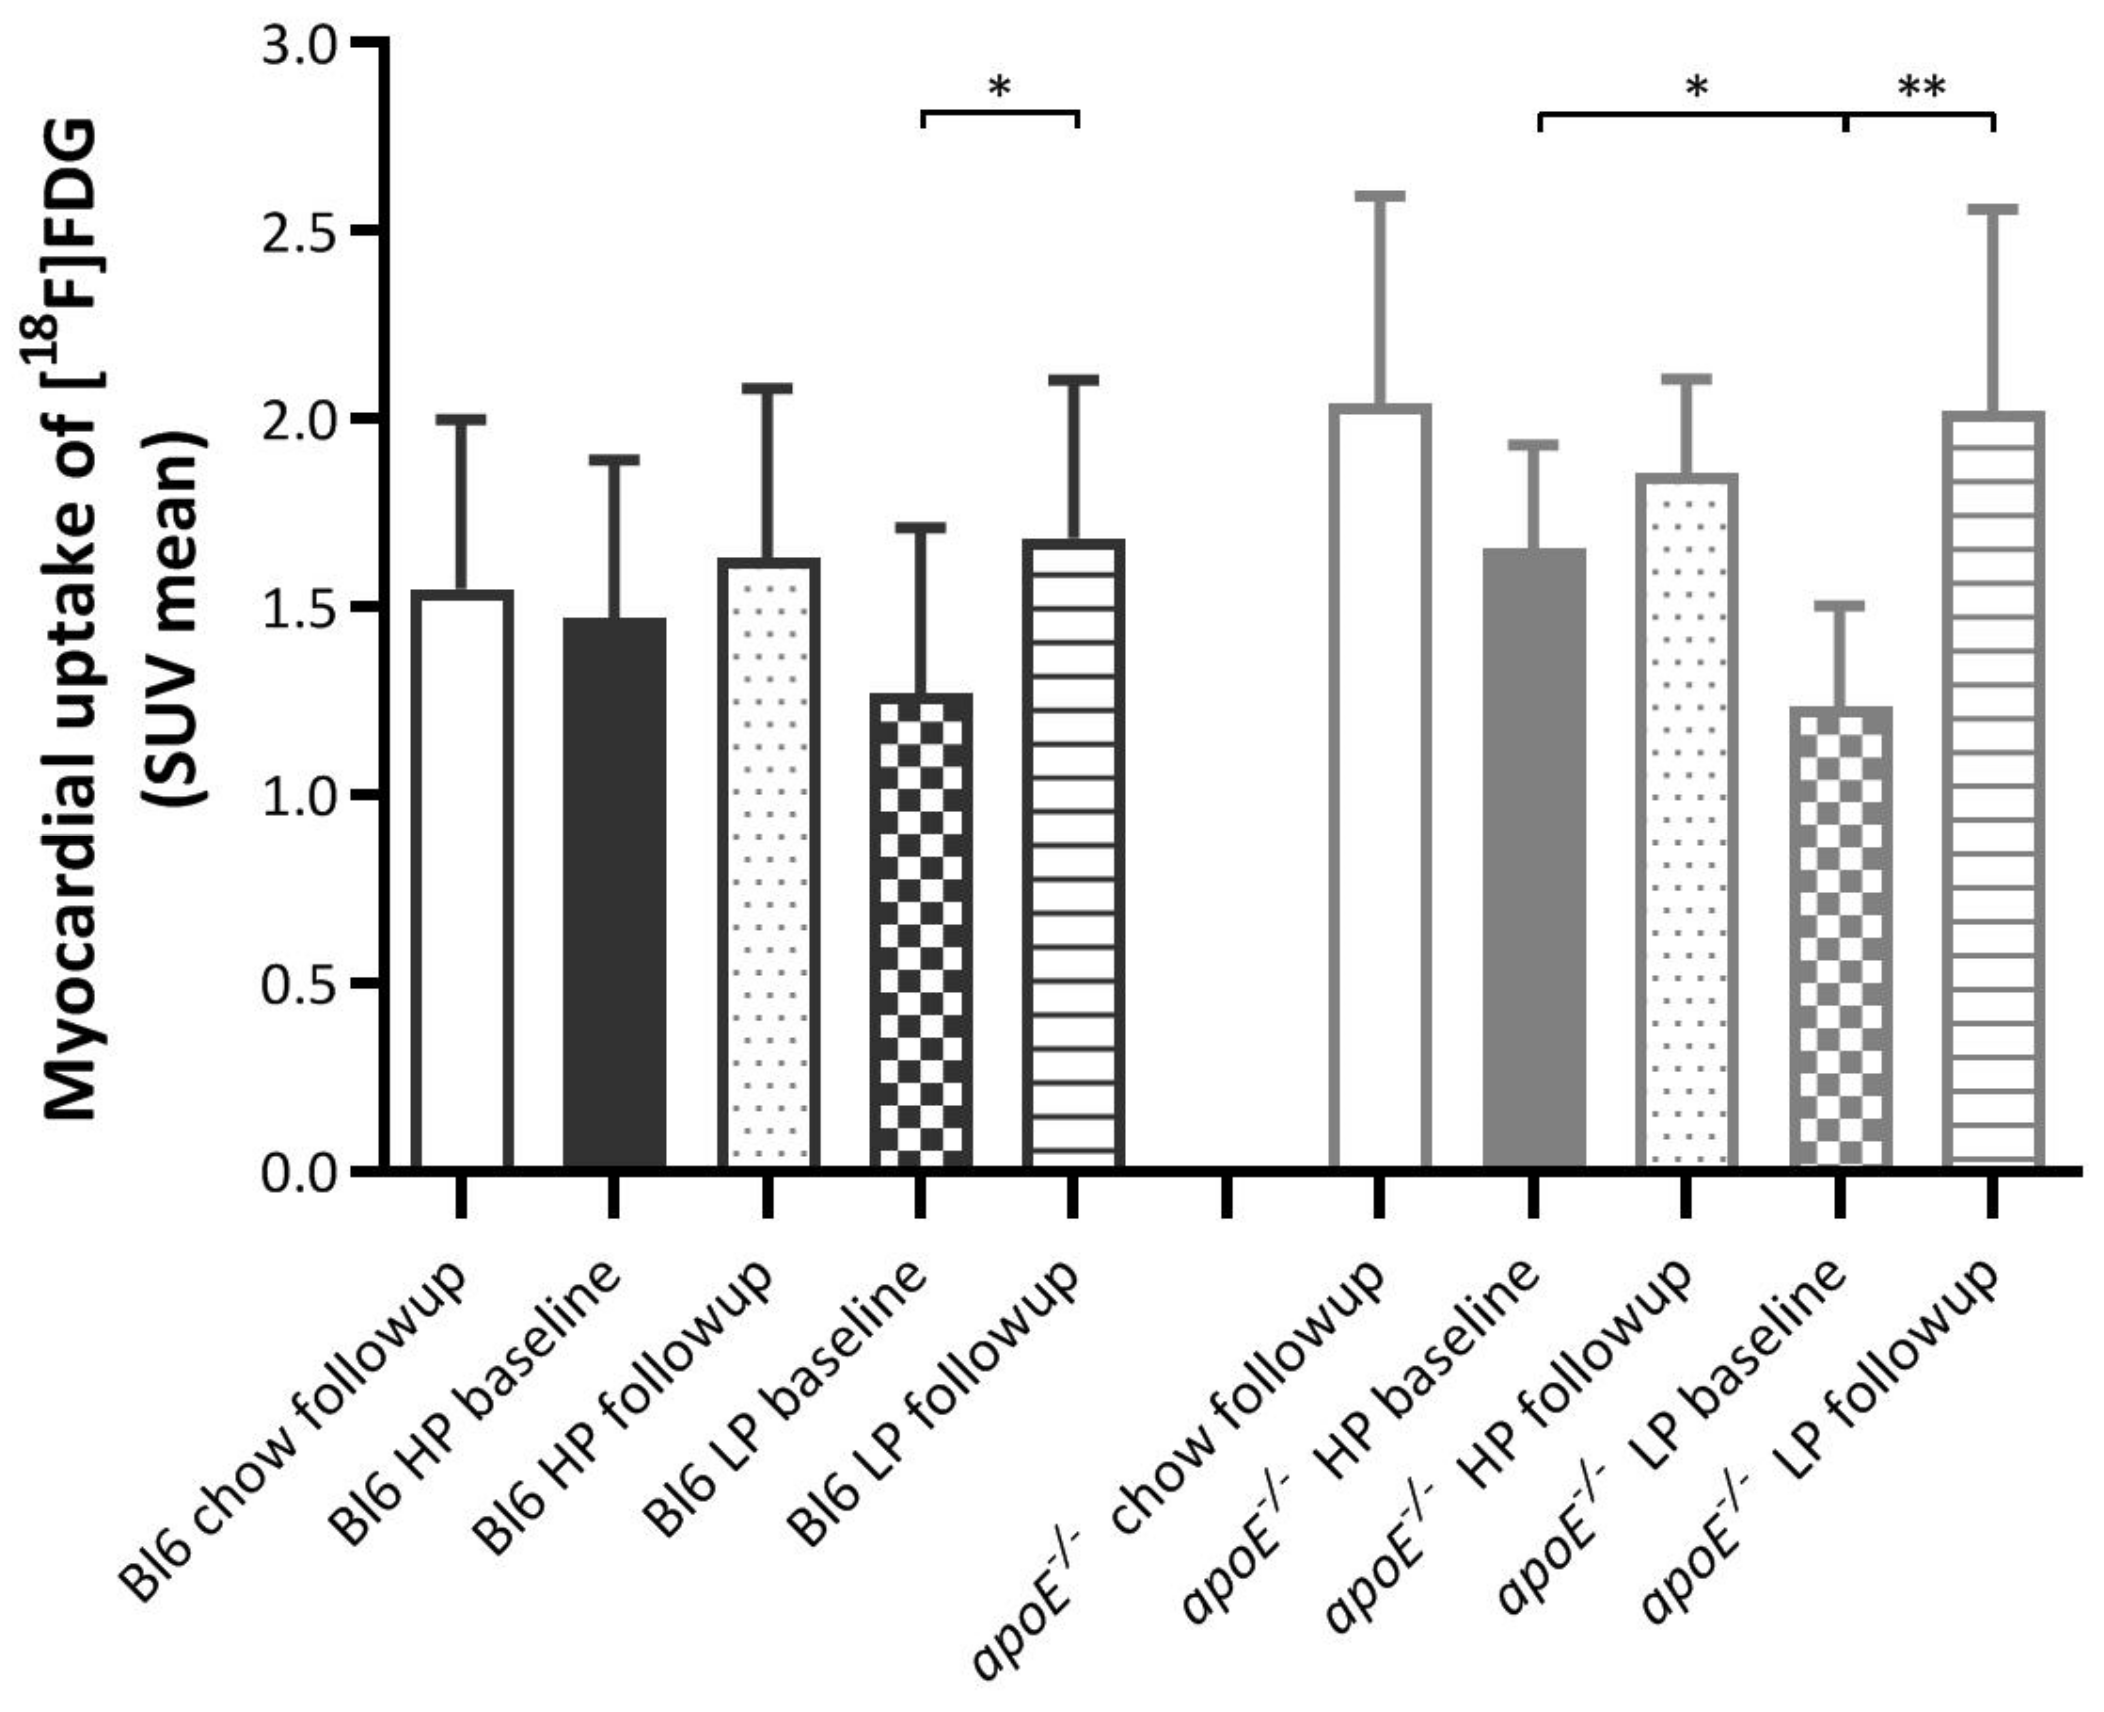

2.1. Effects of Diets on Myocardial [18F]FDG Uptake